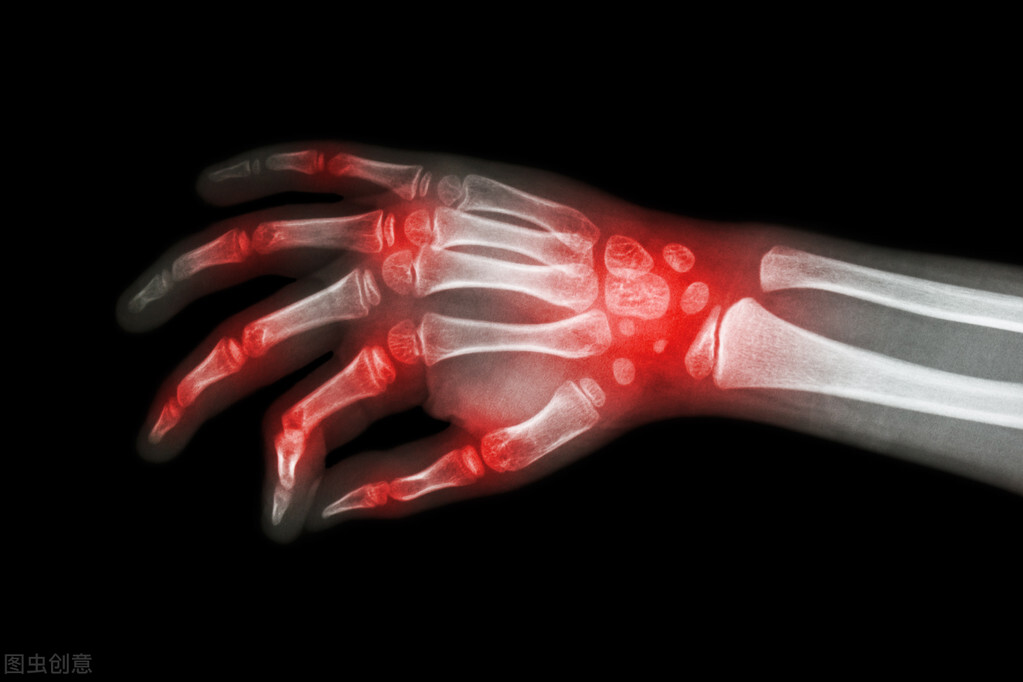

高尿酸血症是嘌呤代谢紊乱引起的代谢异常综合征,非同日2次血尿酸水平超过420umol/L,称之为高尿酸血症。当尿酸浓度过高,可在关节形成尿酸钠晶体并沉积,诱发局部炎症反应和组织破坏,导致痛风;也可在肾脏沉积引发急性肾病、肾结石等,称之为尿酸性肾病。高尿酸血症和痛风是慢性肾病、高血压、心脑血管疾病及糖尿病等疾病的危险因素。